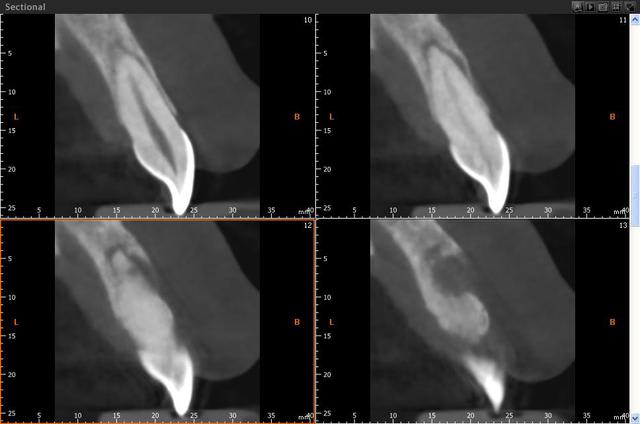

j'ai acheté la vatech lors de l'adf dernier: j'ai la green en 10x8. ça fait le job.

Humator, une image avec métal si tu peux, pour voir les artefacts et qualité de résolution.

voilà un cas avec du metal:couronnes sur les dents bordant l'édentement, et en haut. c'est sur la reconstruction 3d que ça perturbe le plus. Cela dit, tu peux "couper" les artefacts pour les faire disparaitre, si tu souhaites une belle image en volume.

C'est vrai que certaines reconstitutions 3d sont plus moches, quand il y a beaucoup de métal, mais ça ne perturbe pas les coupes.

j'essaye de t'en trouver d'autre bien moches...

ici je n'ai pas "nettoyé" la reconstruction 3d

un autre, où on voit bien les artefacts lié au métal sur la reconstruction, sur les couronnes en bas...

ici c'est un 10x8, ce qui permet de voir assez large

c'est normal que les images soient aussi floues ??

ah oui c'est une vatech!

bon c'est vrai c'est pas cher, mais pour le même prix je préfèrerai la qualité d'acquisition et de traitement; donc planméca avec un champ plus petit 8x8. mais pas une bécane qui ne donne que des images complètements floues.

il ne s'agit pas d'un concours de b... mais il faut quand même avouer que les images sont floues. vu le prix, c'est dommage. ceux qui ont acheté du vatech l'ont fait pour le prix pas pour la qualité.

je suis d'accord avec toi, j'ai vu récemment des images sur cd ( non trafiquées je précise) d'un cbct instrumentarium, les images sont nettement plus nettes. Ils ont même un mode endo ou la définition est assez impressionnante...